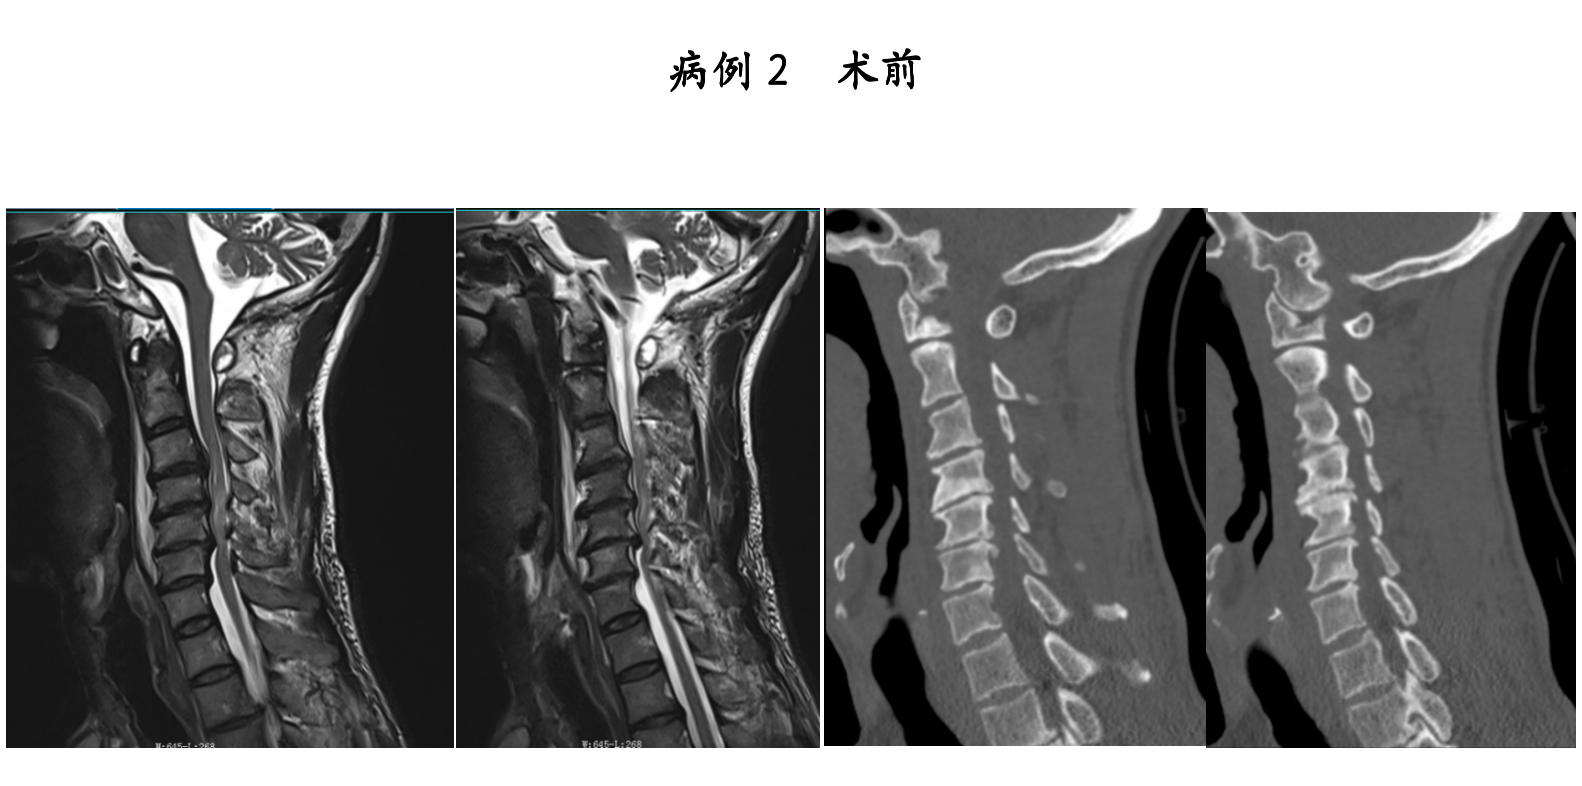

大众卫生报·新湖南客户端3月9日讯(通讯员 匡登峰 申宽宏)近日,祁东县人民医院脊柱外科团队再传捷报。在衡阳市中心医院派驻专家申宽宏副主任医师的带领下,团队成功为2名颈脊髓损伤患者实施了“内镜辅助下颈椎前路减压融合内固定术”。术后患者神经功能恢复良好,疼痛症状显著缓解,康复进程远超预期,赢得了患者及家属的高度赞誉。

颈脊髓损伤是脊柱外科领域的急危重症。由于病变部位毗邻重要的神经和血管,手术操作空间狭小,对精准度的要求极高。传统开放手术虽然有效,但存在创伤大、术后恢复慢等问题,对医生的技术和经验是极大的考验。

高清内镜下“精准拆弹”,实现脊髓“零侵袭”

手术过程中,团队仅通过微小切口建立内镜通道,直达脊柱病变部位。在高清内镜的实时视野下,脊髓、神经根及周围血管等组织结构清晰可见,真正实现了可视化操作。

医疗团队在镜下精准完成了椎间盘/髓核摘除、椎管减压等核心步骤,彻底解除了脊髓与神经的压迫。随后,通过微小切口精准植入融合器与内固定装置,有效重建了脊柱的生理曲度与力学平衡。

相较于传统开放手术,该术式具有创伤小、出血少、疼痛轻、恢复快的显著优势。术中实现了对脊髓的“零侵袭”,极大降低了手术风险,为患者的快速康复奠定了坚实基础。